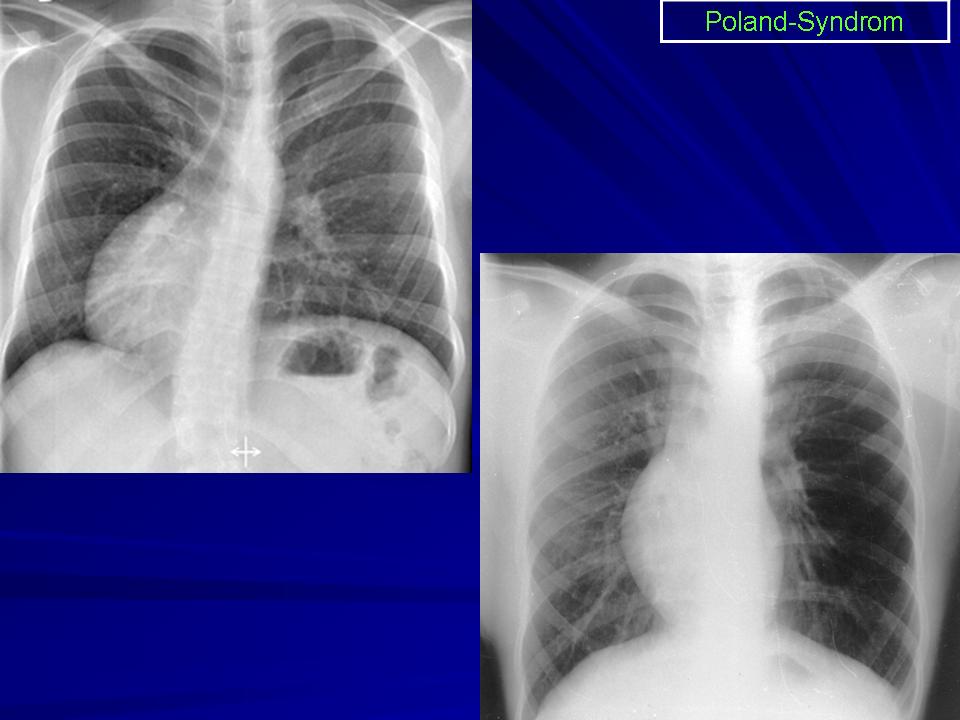

Синдром Поланда (СП) представляет собой комплекс пороков, включающий отсутствие большой и малой грудной мышц, синдактилию, брахидактилию, ателию (отсутствие соска молочной железы) и/или амастию (отсутствие самой молочной железы), деформацию или отсутствие нескольких ребер, отсутствие волос в подмышечной впадине и снижение толщины подкожно-жирового слоя. Отдельные компоненты этого синдрома впервые были описаны Lallemand LM (1826) и Frorier R (1839). Однако назван он по имени английского студента-медика Alfred Poland, который в 1841 году опубликовал частичное описание данной деформации. Полную характеристику синдрома в литературе впервые опубликовал Thompson J в 1895 году.

Катенёв Валентин Львович wrote:

Слева нет тени большой грудной мышцы и это 100-пудово Поланд?